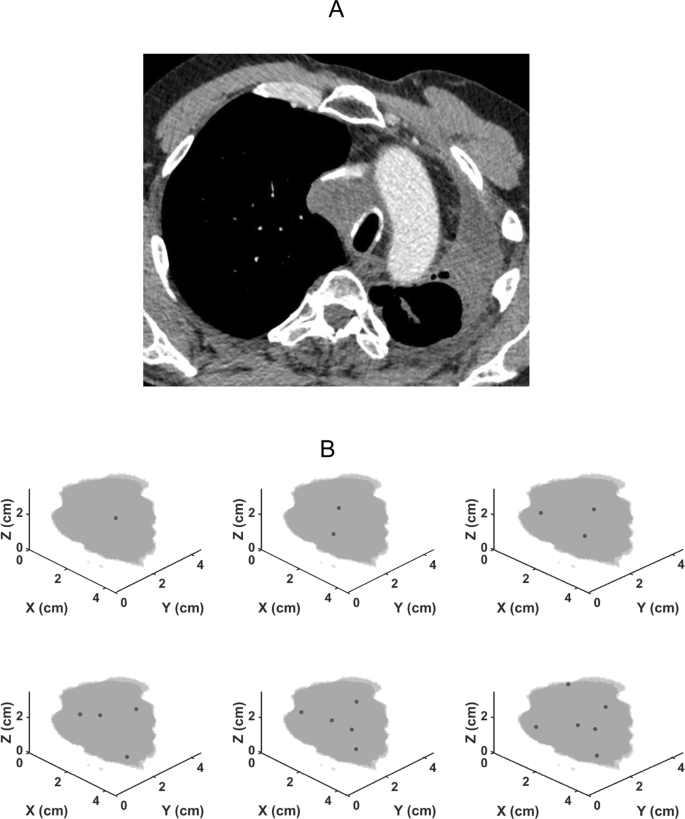

The patient also underwent a high-resolution computed tomography (CT) scan of the thorax from which the location, size and 3D shape of the lung tumor was accurately determined. We used MATLAB 2015b (The MathWorks, Natick, MA, USA) to create a geomerically accurate representation of the tumor boundary from the CT image.

Figure 3 shows renditions of the lung tumor in the patient we studied along with the optimal locations of cisplatin injection sites for 1 to 6 injections calculated using the computational model with the values of \({V}_{f}\), \({k}_{i}\) and \({k}_{{\rm{f}}}\) given above. Note that a single injection is optimally located close to the middle of the tumor while multiple injections are distributed in a balanced way thoughout the tumor mass, as one would expect intuitively. The major benefit of multiple injections, however, is evident in Fig. 4 which shows the total cisplatin dose required to kill all tumor cells as a function of the number of injections. This dose decreases by more than 3 orders of magnitude in going from 1 to 5 injections. Relatively little additional dose reduction is achieved by going to 6 injections, however.

The most important finding of our study, however, is the enormous apparent benefit of apportioning a given dose of cisplatin between a number of well-placed injections rather than delivering the entire dose into a single central location, as shown in Fig. 3. Indeed, our model predicts that the dose of cisplatin required to kill a given fraction of tumor cells using 5 injections can be 3 orders of magnitude less than that required for a single injection (Fig. 4). At 6 injections we appear to be approaching the point of diminishing returns, but these results provide compelling evidence that EBUS-TBNI should not be limited to a single injection site in the treatment of lung cancer. This conclusion is further supported by the results shown in Fig. 5 which indicate that increasing the number of injections has a marked effect on the robustness of treatment efficacy in the presence of variations in the local lethal concentration of cisplatin; 5 or more injections are predicted to be almost uniformly efficacious over the range of \({\phi }_{t}\) studied while a single injection is relatively fragile in this respect. Of course, these results are predicated on the cisplatin injections being delivered at the optimal sites predicted by our model. On the other hand, the locations of these optimal sites are distributed roughly uniformly throughout the body of the tumor (Fig. 3). It may therefore be that empirical placement of injections guided simply by the principle of uniform distribution will be close enough to optimal that most of the predicted gains of multiple injections will be realized.